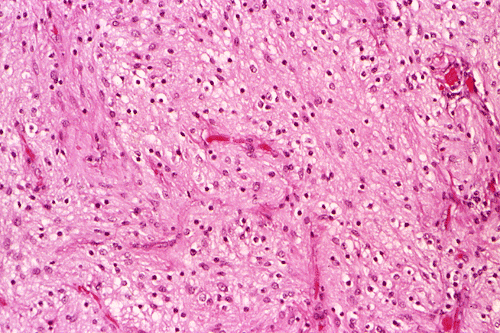

These photos were obtained from the formalin fixed paraffin embedded sections.

Com401-2-Perm01.gif (145631 bytes) Com401-2-Perm02.gif (137202 bytes) Com401-2-Perm03.gif (136949 bytes) Com401-2-Perm05.gif (135940 bytes) Com401-2-Perm06.gif (133968 bytes) Com401-2-Perm07.gif (137355 bytes)